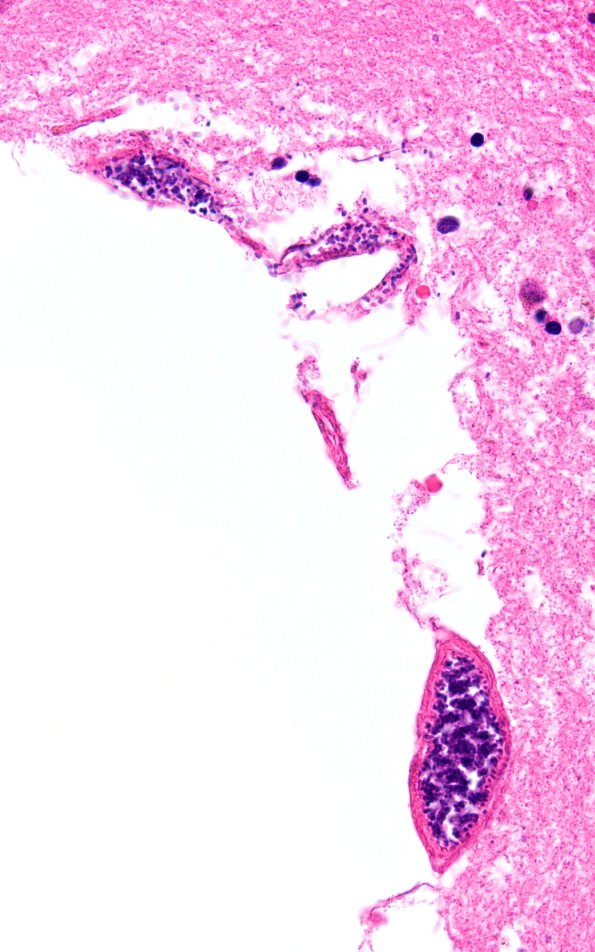

Washington University Experience | BASIC PROCESSES | Artifacts | Artifact - Swiss Cheese Brain | 34B7D Swiss Cheese Brain (Case 12) N13 60X 2A

Several magnifications of a typical cystic lesion show typical bacteria within the adjacent vasculature. (H&E)